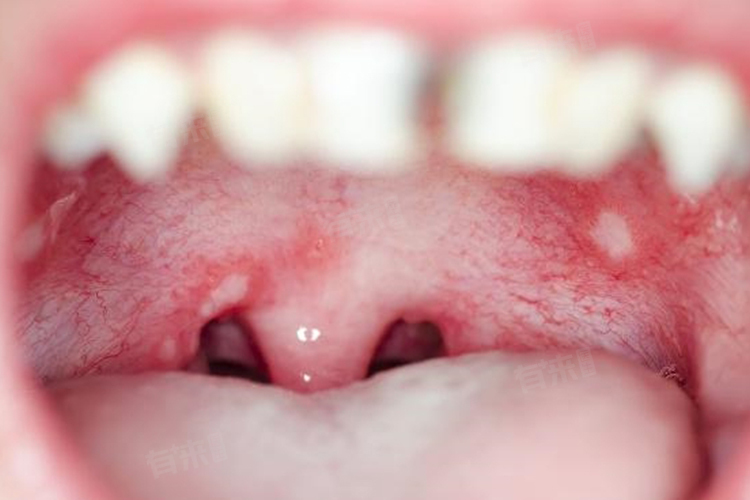

口腔溃疡白色的创面可能是由多种原因导致的,主要包括组织坏死、假膜脱落、溃疡面周围色素沉着等,可以通过一般治疗、药物治疗等措施进行改善。

- 组织坏死:当口腔溃疡没有得到及时治疗,溃疡面积可能逐渐扩大并发生坏死,坏死组织脱落后会形成白色的假膜覆盖在溃疡面上,通常伴有溃疡面积较大、疼痛明显等症状。

- 假膜脱落:在口腔溃疡的愈合过程中,表面可能会形成一层白色的假膜,随着溃疡的逐渐愈合,假膜可能会脱落,露出下方的白色创面。

- 口腔溃疡较深:口腔溃疡发生时,如果溃疡较深、面积较大且病程较长,愈合后可能留有白色瘢痕。